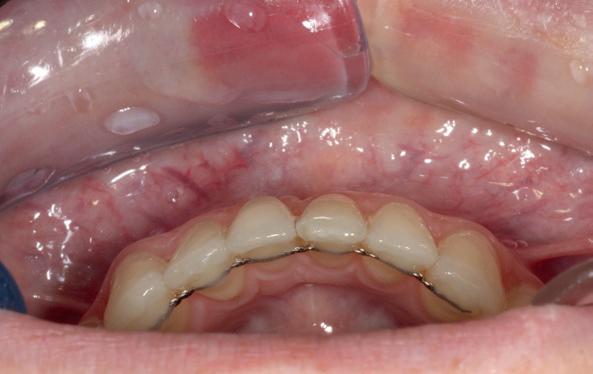

Klinische observaties en literatuur (o.a. Teughels et al., 2009; Engelking & Zachrisson) tonen aan dat zodra de wortel van een element buiten het corticale bot wordt gebracht, het lichaam deze positie niet corrigeert met spontane botgroei. In plaats daarvan treedt botresorptie op, gevolgd door mucogingivale problemen. Patiënten die jaren na een orthodontische behandeling terugkomen met gingivarecessies, mobiliteit of wortelcariës blijken vaak onbewust slachtoffer van een (soms door retentie versterkte) standswijziging die torque-gerelateerd is. Met name bij een dun gingivaal biotype is de biologische tolerantie minimaal.

De bonded retainer speelt een centrale rol in deze

1. Onderfront pre-orthodontisch: zichtbare gingivarecessie bij de 31 ten gevolge schending van de biologische envelop.

2. Occlusale opname onderfront: standswijzigingen bij de 32 en de

31 door een geactiveerde retentie draad.

3. (Lokale) orthodontie leidt tot adequate standscorrectie met afname van de gingivarecessie bij de 31

problematiek. Hoewel bedoeld om stabiliteit te waarborgen, fungeert de retentiedraad bij loslating of vervorming geregeld als actieve orthodontische krachtbron. Elastic deflection of spanningsopbouw door parafunctie kan ongecontroleerde bewegingen veroorzaken waarbij tanden letterlijk “schommelen” rond een verstoorde as. Het gevolg: wortels die buccaal of linguaal buiten de botbegrenzing worden gedrukt met parodontale schade als gevolg.